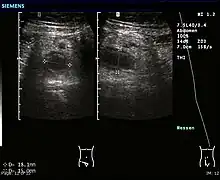

- l’échographie apporte des arguments de diagnostic différentiel, et aide au diagnostic d’abcès appendiculaire ;

- le scanner abdominal peut montrer un aspect de masse de la fosse iliaque droite. Cet examen tend à se généraliser en raison d'une très bonne fiabilité[55] Ailleurs, le scanner peut aider au diagnostic différentiel (tumeur cæcale, iléite terminale, maladie de Crohn, adénite mésentérique, etc.) ;